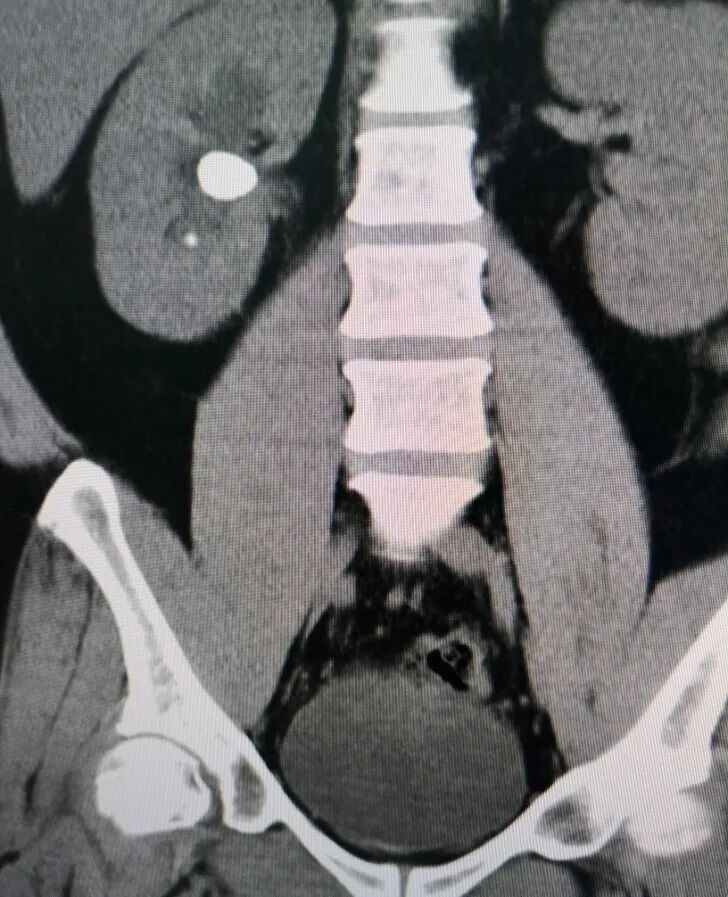

尿系结石往往是急性发作,出现比较剧烈的腰腹部疼痛、恶心呕吐,有时会伴有发烧等等,需要第一时间到医院进行就诊,通过超声、CT、血尿常规等进一步明确诊断。

如果是一种单纯的肾结石或者输尿管结石,可以根据结石的大小、位置选择不同的治疗方法。

结石小于0.6cm,原则上可以保守治疗,比如多喝水、多运动、服用一些排石的药物,一部分病人的结石是可以自行排出的。

治疗方法比如体外冲击波碎石、经皮肾镜、输尿管镜等微创技术。如果结石比较大,超过0.6cm大小,很难自行排出体外,就不要勉强采用药物等保守的治疗方法。